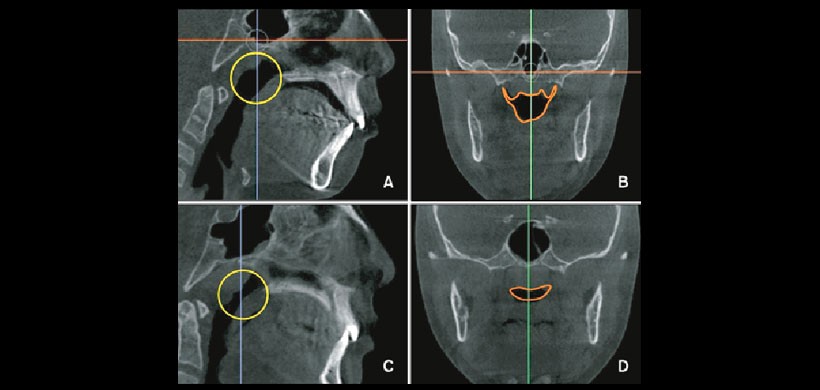

Diversos estudios realizaron una clasificación de la hipertrofia adenoidea mediante el uso de la Nasoendoscopia. Éste examen auxiliar es considerado el “gold estándar” para determinar la severidad de la hipertrofia adenoidea. Major MP, et al. recoge las clasificaciones mediante la Nasoendoscopia y realiza la validación mediante la TCHC (ver cuadro 1).La mencionada clasificación está basada en la relación existente entra el tejido adenoideo y las estructuras adyacentes tales como el torus tubaris, el vómer y el paladar blando (ver figura 1 y 2)

Se puede utilizar la tomografía computarizada de haz cónico como herramienta de diagnóstico y de evaluación de la severidad de la hipertrofia adenoidea y el grado de obstrucción a nivel de la nasofaringe e informar al paciente oportunamente para realizar la interconsulta respectiva a la parte médica para evitar las posibles complicaciones. Se podrá establecer protocolos de estudios y de trabajo en pacientes pediátricos para descartar ésta patología.

Figura 3: Evaluación tomográfica de la vía aerea nasofaringea. A, se aprecia el aumento de tamaño de la adenoide, en B, se aprecia un via aerea amplia. C, se aprecia un crecimiento mayor de la adenoides y en D, se observa una configuracion mas estrecha de la vía aérea.